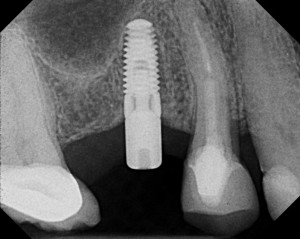

- Dental Implants help prevent bone loss because it preserves and protects the bones on the area where a tooth was extracted. In doing so, the natural strength and shape of the bone and jaw are maintained.

- Dental Implants reduce the load on the patient’s remaining teeth since they are attached into the jawbone unlike bridges and dentures that solely depend on the surrounding remaining teeth and gum. Because of this, the neighboring teeth are safe from deterioration from too much strain.